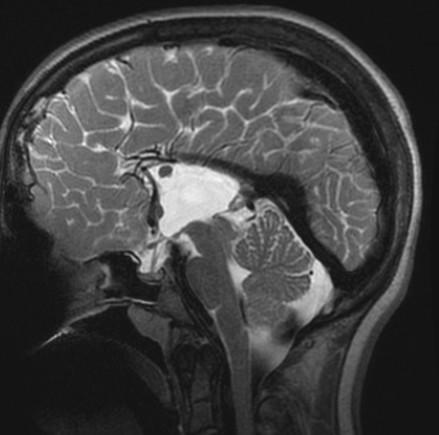

Remember to start with Sweep the Midline… Where is the anterior commissure?

Always finish the sweep looking for second anomaly…

Parallel ventricles

Radial or pallisading gyri in sagittal plane

Colpocephaly

Longhorn or Viking helmit frontal horns

High riding 3rd vent

“Keyhole” temporal horns

Vascular anomalies: “wandering ACAs”

All 3 commissures are absent.

Cingulate gyrus (black arrows) “mirrors” the development of the corpus callosum.

Enlarged HC connects fornices, not cerebral hemispheres